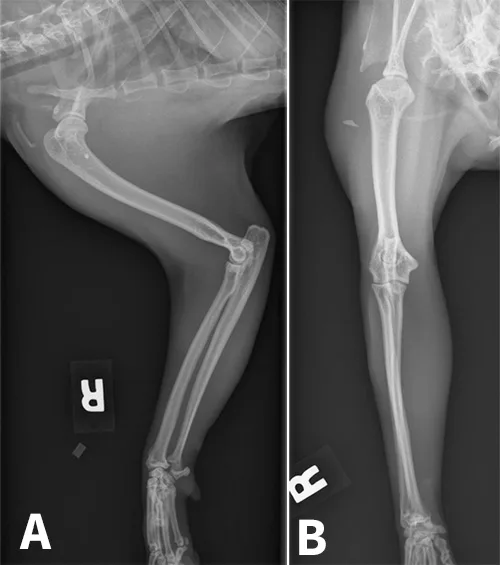

Soft tissue swelling was present lateral to the midscapula, extending to the level of the carpus. A triangular mineral opacity, measuring approximately 4 × 8 mm, was seen lateral to the proximal humerus in the craniocaudal view and superimposed over the humerus in the lateral view (Figures 2A and B). No fracture, luxation, or other osseous abnormality was detected. The findings were interpreted as abscessation and/or cellulitis secondary to a penetrating foreign body.

Figure 2: Left lateral (A) and craniocaudal (B) radiographs of the humerus demonstrating radiopaque foreign material (arrow)